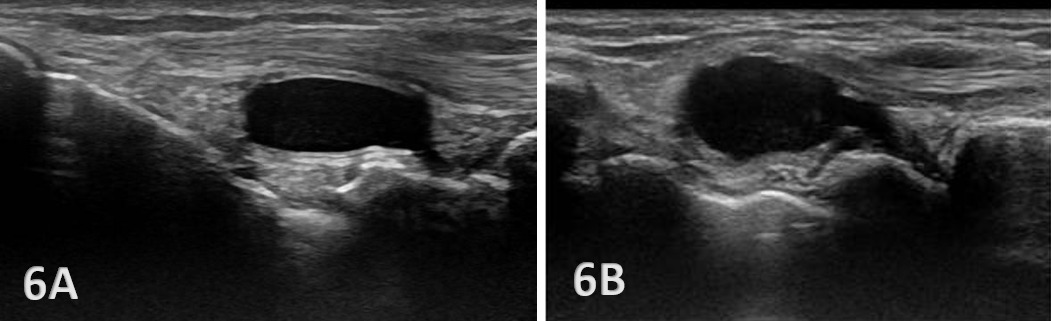

Anechoic or hypoechoic joint effusion and/or synovitis (synovial hypertrophy) and cysts within the joint.

Joint effusion is somewhat compressible and mobile when transducer pressure is applied to the area. This is different from synovitis, which appears as hypoechoic or isoechoic, non-compressible tissue within the joint recess. Synovitis may be associated with conditions such as rheumatoid arthritis, psoriatic arthritis, or other inflammatory arthropathies. Lastly, a ganglion cyst may appear as a well-defined, round or lobulated cystic structure with anechoic or hypoechoic internal contents. The cyst will usually have a small, smooth wall and exhibit posterior acoustic enhancement. These cysts will typically be minimally or non-compressible and painful.